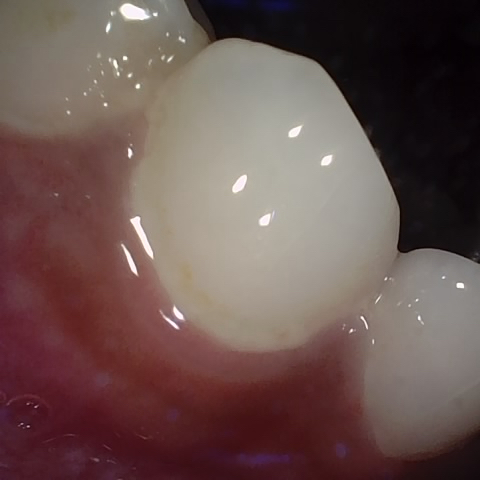

Annotated as "Good"